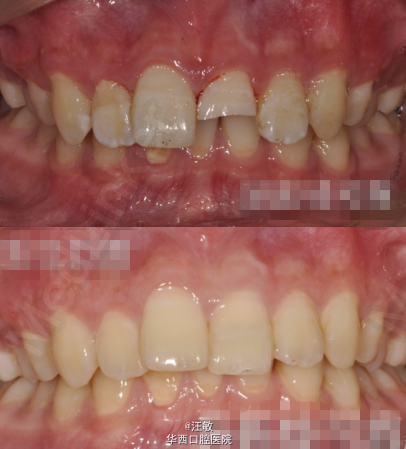

患者男,12岁,21牙外伤折断露髓,进行根管治疗后用树脂材料直接将碎片与剩余牙体组织粘接。 此方法虽能够最大限度的保留牙体组织,但也存在一定局限性,例如牙体变色,碎片再脱落,不能承受过大咬合负荷。